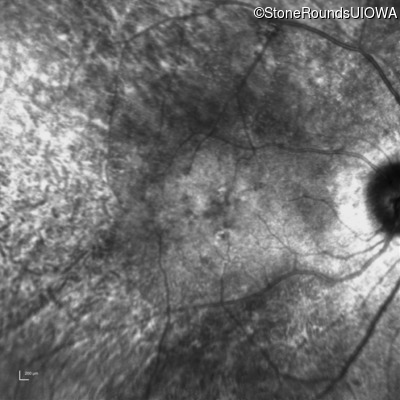

AD Retinitis Pigmentosa (IA1aii)

Age at visit: 53 years

This 53 year old woman first came to attention when she had difficulty walking down stairs. A few years later she noticed difficulty seeing in dim light.

Diagnosis & molecular findings

AD Retinitis Pigmentosa PRPH2 Pro216Ser CCT>TCT   AD